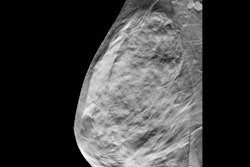

Example of an interval cancer retrospectively detected by an AI algorithm. A 41-year-old woman presented for a screening digital breast tomosynthesis (DBT) examination; its findings were interpreted as negative. Ten months later, the patient presented with a lump in the left breast and was subsequently diagnosed with grade 3 invasive ductal carcinoma. At retrospective evaluation of the initial screening

mammogram, the AI algorithm marked a suspicious lesion (white outline) in the left breast, with high scores of 81 on the craniocaudal view and 75 on the mediolateral oblique view. This area of architectural distortion corresponds to the cancer that was subsequently diagnosed.RSNA